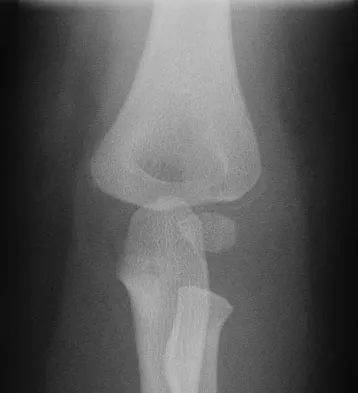

A 39-year-old woman fell onto her flexed elbow and sustained a comminuted displaced radial head and neck fracture. Radiographs confirm concentric reduction of the ulnohumeral joint. Examination reveals pain with compression of the radius and ulna at the wrist. What is the best treatment for the radial head fracture?

Explanation

Patients with comminuted radial neck and head fractures and associated wrist pain have a significant injury to the elbow and forearm. Nonsurgical management is an option, but initial casting will result in stiffness and early range of motion is likely to be unsuccessful secondary to pain. Surgical treatment with open reduction and internal fixation, although possible, is technically demanding and results are unpredictable with comminuted fractures. Excision alone in the face of wrist pain may lead to radial shortening. The treatment of choice is excision and metallic radial head arthroplasty. Silastic implants have been associated with synovitis and wear debris. Furry KL, Clinkscales CM: Comminuted fractures of the radial head: Arthroplasty versus internal fixation. Clin Orthop 1998;353:40-52.